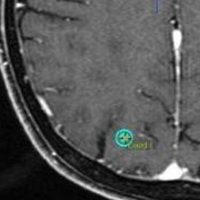

放射線外科 SRS の治療計画です。左側のとても小さな脳転移にたいして,中心線量25グレイ,辺縁線量20グレイの計画です。黄色の線より外にはほとんど放射線が入らない治療です。でも周辺脳が全く被曝しないわけではありません。